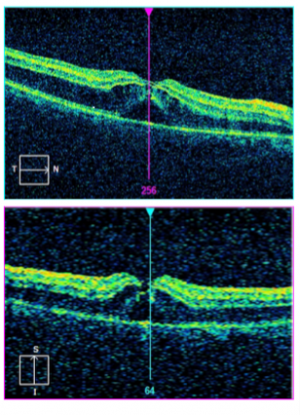

Optical coherence tomography (OCT)

Optical coherence tomography (OCT) is a non- contact, high-resolution and cross-sectional imaging modality that utilizes low coherence interferometry principle. It can achieve axial resolution in the range of 3–20 μm.[12]Posterior segment OCT (PSOCT) uses a lower wavelength of light at 830 nm while Anterior Segment OCT (ASOCT) uses a higher wavelength 1310 nm.

Anterior Segment Optical Coherence Tomography (ASOCT)

In ocular trauma, ASOCT helps to support the diagnosis of ocular surface injuries and intraocular lesions. It has advantages of accuracy, repeatability and can be performed in penetrating ocular injuries as it is non-contact imaging technique. ASOCT can be used to visualize Descemet’s membrane detachment or angle closure in the presence of hazy cornea. Other conditions that may be diagnosed with ASOCT include corneal intrastromal foreign bodies, its depth, up to 6mm [2][13],localization and presence of residual foreign bodies, damage to the angle structures and the presence of cyclodialysis cleft.

In clinical situations where gonioscopy can be quite challenging such as in the presence of hypotony from cyclodialysis clefts resulting in a shallow anterior chamber precluding visualization of the iridocorneal angle, ASOCT may be a great alternative or adjunctive modality to evaluate the angle anatomy.[14]

Limitations of ASOCT however include inability to penetrate pigmented tissue and inability to image past the posterior pigmented epithelium of the iris.

Posterior segment Optical Coherence Tomography (PSOCT)

In ocular trauma, posterior segment OCT may aid in diagnosing and assessing Berlin’s edema [15], macular hole[16] [17], preretinal or submacular hemorrhage, retinal detachment, direct or indirect choroidal rupture [18] [19] ,choroidal detachment, retinal pigment epithelial tears [20], optic disc pit or traumatic retinoschisis. It is easy, quick and reliable tool for diagnosis and monitor macular and chorioretinal disease with high accuracy and precision.